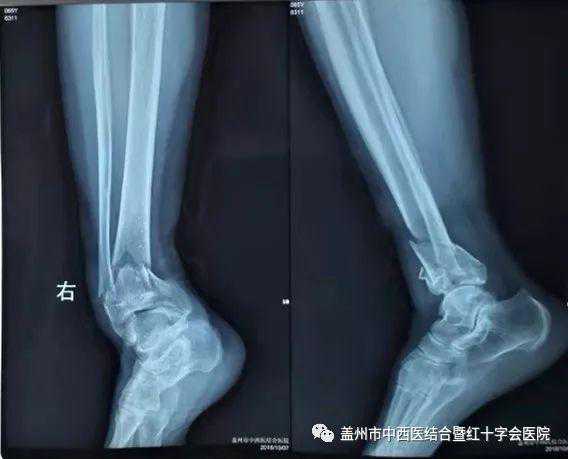

10月12日,盖州市中西医结合医院骨三科主任陈永博,在骨科专家施继明的指导下,成功为一名右胫腓骨远端粉碎性骨折的病人实施了切开复位钢板螺钉内固定术,术后效果非常好。据业内人士了解,该手术具有很高的技术含量,难度系数较高。